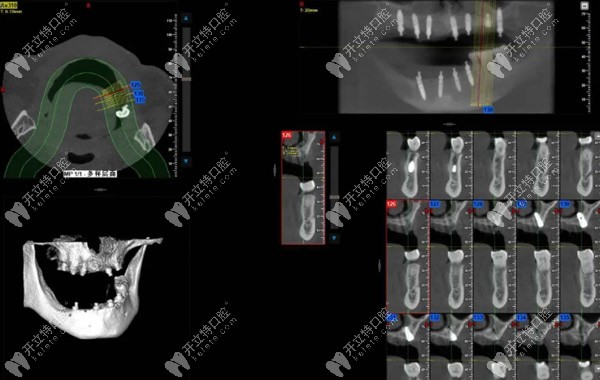

院長進(jìn)一步根據(jù)術(shù)前檢查,用雅悅的“AI數(shù)字化一站式定制中心”的CBCT設(shè)備獲取口腔數(shù)據(jù)進(jìn)行分析。

牙齒缺損位置:15,14,12,11,12,13,14,17,部分牙齒松動(dòng),46可用骨高度大于13mm,骨寬度7-9mm,其余骨高度、寬度尚可。

梁先生術(shù)后ct▲